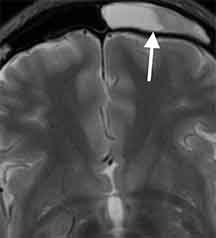

前頭洞炎

43歳女性、左の額の痛みで受診。頭部MRI検査で左前頭洞に炎症性変化を認めました。

副鼻腔炎による頭痛

このような鼻腔から離れた前頭洞炎の場合には、鼻水や鼻づまりはない事があります。